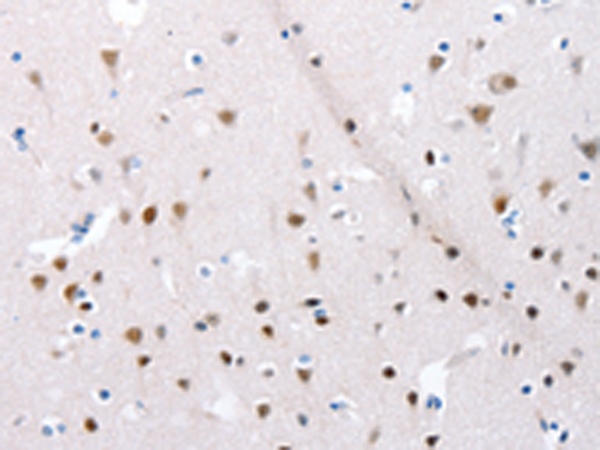

分类: 科研抗体货号: P11041别名: LPH, MSH, NPP, POC, ACTH, CLIP应用: WB,IHC反应种属: Human, Mouse